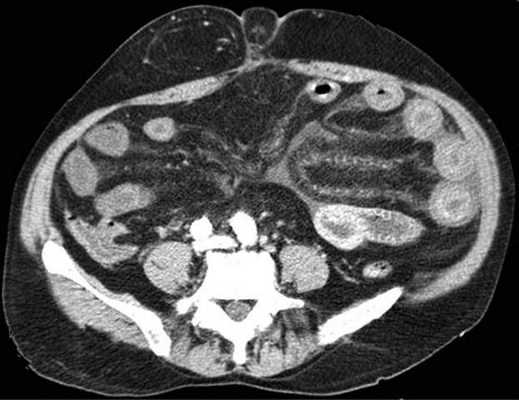

Осложнённая форма (чаще всего в результате странгуляции)

Для странгуляции тонкой кишки характерны утолщение стенок кишечника, васкулярные нарушения и выраженные патологические изменения в брыжейке и в брюшной полости. Диагностические находки включают в себя:

-расширенные петли тонкой кишки проксимальнее транзиторной зоны (зоны обструкции);

-спавшиеся петли кишечника дистальнее уровня обструкции;

-транзиторная зона;

-смешанный характер стаза содержимого кишечника в расширенных петлях с преобладанием жидкостного компонента;

-утолщение стенки кишки циркулярного типа. Важно помнить, такой тип утолщения стенок тонкой кишки при непроходимости как правило связан с сосудистыми нарушениями;

-нарушение нормального контрастного усиления стенок кишки. Изменения варьируют от гиперконтрастирования до полного отсуствия контрастного усиления. Различные варианты этих изменений между описанными выше крайностями могут наблюдаться одновременно в разных сегментах тонкой кишки. Полное отсутствие усиления означает артериальный рефлекторный спазм и свидетельствует в пользу тяжести поражения;

-петля с утолщенными стенками теряет свою эластичность и становится ригидной, вытянутой;

-пристеночный пневматоз тонкой кишки, в особо тяжелых случаях появляются интрамуральные пузырьки газа;

-появление патологических плотностей в брыжейке в виде распространяющихся матовых инфильтратов и тяжистости за счет кровоизлияний в жировые ткани;

-застойные изменения сосудов брыжейки. Сначала диаметр сосудов увеличивается, но со временем наступает рефлекторный артериальный спазм, брыжейка будет выглядеть с обеднённой васкуляризацией. Сосуды сужены или с полностью коллабированным просветом;

-газ в просвете верхней брыжеечной вены;

-газ в просвете портальной вены;

-при заворотах нарушается нормальная сосудистая анатомия брыжейки. Сосуды как бы закручиваются вокруг оси заворота и тянут за собой измененный брыжеечный жир- по типу раковины улитки или торнадо. Для большей наглядности представьте себе кусок расправленной ткани на столе, которую вы прижали пальцем и начали закручивать не отрывая ваш палец от стола. На КТ сканах часто можно увидеть характерный признак конусовидной спирали (whirl sign);

-свободная жидкость в карманах брыжейки и в брюшной полости. Иногда жидкость может быть повышенной плотности за счет геморрагического компонента.

примеры странгуляционной осложнённой непроходимости с характерными изменениями в брыжейке, внутрибрюшинном жире, утолщением стенок тонкой кишки и нарушением контрастного усиления.

Закручивание сосуда при завороте